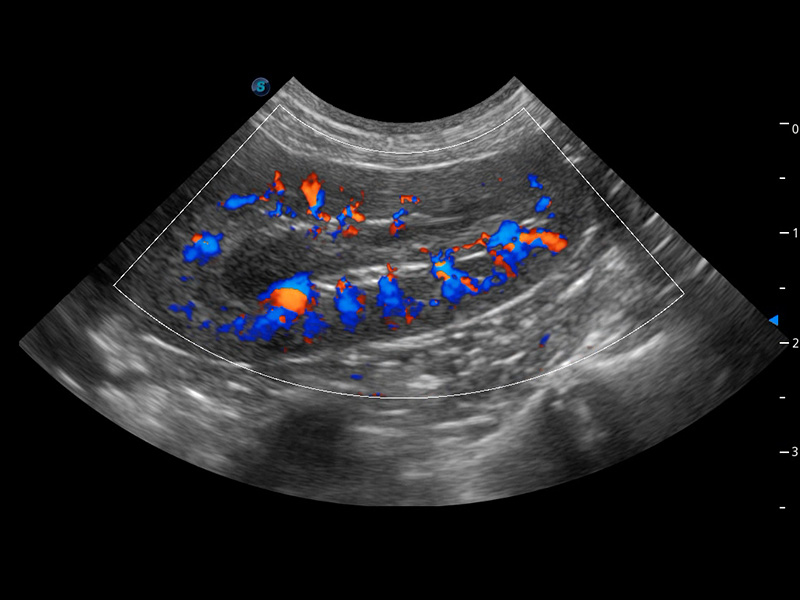

ProPet 60 作为一款高端台式动物超声设备,为动物医生的日常诊断提供了一系列贴合动物临床需求、解决临床实际问题的高级成像功能。凭借全系列高清探头,满足医生对腹部、心脏、生殖、浅表、肌骨等成像的所有需求,切实帮助您提升检查效率,提高诊断信心。

兽用彩色多普勒超声诊断系统

动物是人类最亲密的朋友和最值得信赖的伙伴。milan米兰也一直致力于探索动物专用的超声影像解决方案。 全新推出的ProPet系列,是milan米兰在动物超声影像智能化、专业化、精准化的一次跨越式革新。动物不能用言语来表述自己的不适,通过超声影像,ProPet系列搭建了动物医生与不同物种沟通的“桥梁”,为动物医生注入了“治愈之力”。